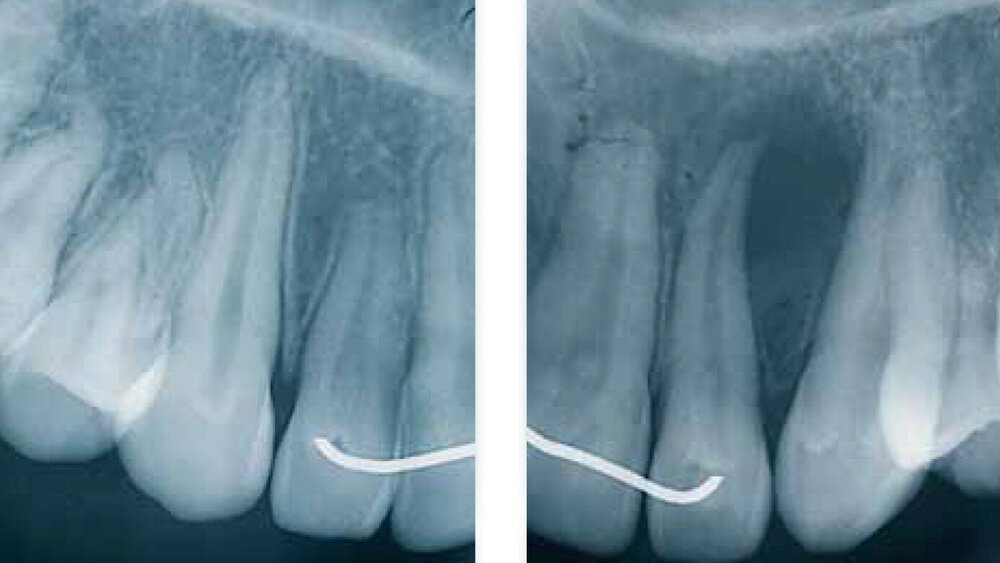

Die GZ wurde auch der parodontalen Zyste gegenübergestellt. Während letztere zwischen den Wurzeln sämtlicher Zähne entstehen kann, erscheint die GZ typischerweise nur zwischen dem lateralen Schneidezahn und dem Eckzahn, dort wo sich Prämaxilla und Maxilla vereinen. Es wurde Wert darauf gelegt, dass die Zyste zwischen parodontal und pulpal gesunden Zähnen vorkommt und somit ein Zweifel an ihrem fissuralen Ursprung ausgeschlossen ist. Die GZ verdrängt die Wurzeln des lateralen Incisivus und des Eckzahns, was als erstes klinisches Zeichen beschrieben wird. Später kann es zu einer Vorwölbung der vestibulären Schleimhaut kommen, oft assoziiert mit einem Druckgefühl (Abb. 1 bis 5).

Die klinische und pathohistologische Evidenz spricht überzeugend dafür, dass Zysten im „Globulomaxillären Bereich“ radikuläre Zysten, laterale Parodontalzysten, odontogene Keratozysten [Christ, 1970], kalzifizierende odontogene Zysten, adenomatoide odontogene Tumore [Rosenberg & Cruz, 1963; Giansanti et al., 1970; Khan et al., 1977], odontogene Myxome [Rud, 1964; Taicher & Azaz, 1977], Ameloblastome [Aisenberg & Inman, 1960], zentrale Riesenzellgranulome oder hämorrhagische Knochenzysten [Peters & Wassow, 1968] sind (Abb. 6 bis 13).